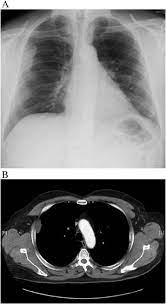

Localized Malignant Pleural Mesothelioma Mimicking An Anterior Mediastinal Tumor Sciencedirect

Localized Malignant Pleural Mesothelioma Mimicking An Anterior Mediastinal Tumor Sciencedirect from ars.els-cdn.com